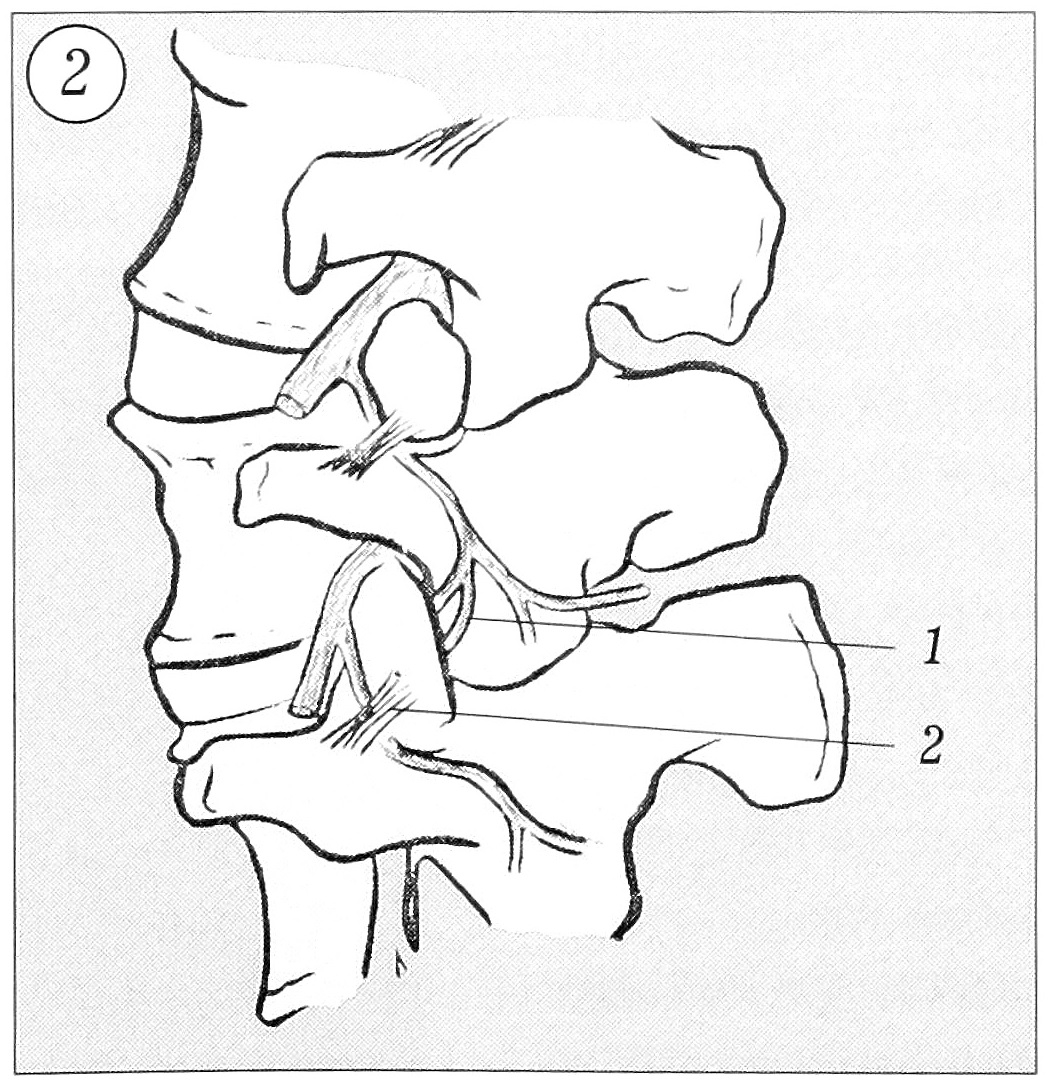

Иннервация межпозвонкового сустава обеспечивает его участие в проприоцептивных и ноцицептивных процессах. Источник иннервации — медиальная веточка задней первичной ветви спинального нерва [13, 15, 49]. Медиальная веточка задней ветви (от L1 до L4) спускается через борозду в основании поперечного отростка позвонка, покрыта мамиллоакцессорной связкой на передненижнем краю фасетки этого же уровня. Данная связка — часть межпоперечной мембраны. На этом уровне одна или две маленькие нервные веточки идут к фасетке. Медиальная спускающаяся ветвь затем продолжается каудально, пересекает дугу и делится на несколько ветвей, которые иннервируют паравертебральные мышцы, межостистые связки, посылает несколько тонких вето- чек к медиальной и задней поверхности нижнего сустава, а также к коже паравертебральных зон (рис. 2). Таким образом, каждая задняя ветвь иннервирует по крайней мере две фасетки и каждая фасетка получает иннервацию по крайне мере от двух спинальных уровней.

Рис. 2. Схема иннервации дугоотростчатого сустава [37]. Медиальная веточка (1) продолжается дистально и посылает множественные тонкие веточки к медиальной поверхности верхнего отдела фасетки (2).